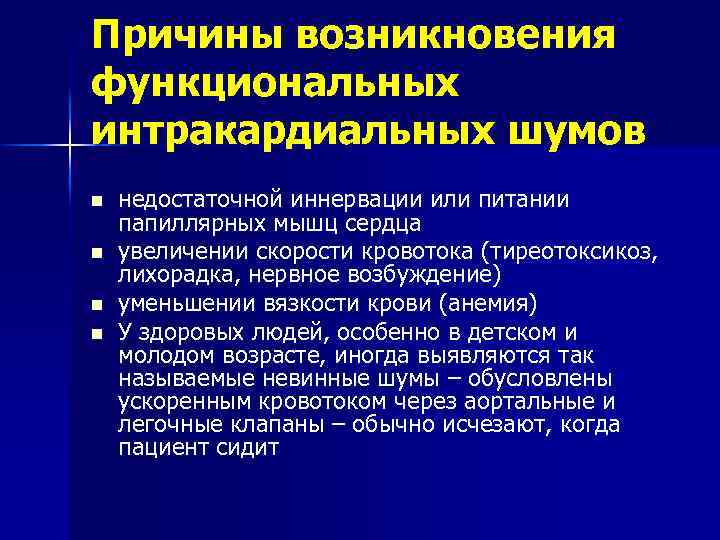

Причины возникновения функциональных интракардиальных шумов n n недостаточной иннервации или питании папиллярных мышц сердца увеличении скорости кровотока (тиреотоксикоз, лихорадка, нервное возбуждение) уменьшении вязкости крови (анемия) У здоровых людей, особенно в детском и молодом возрасте, иногда выявляются так называемые невинные шумы – обусловлены ускоренным кровотоком через аортальные и легочные клапаны – обычно исчезают, когда пациент сидит